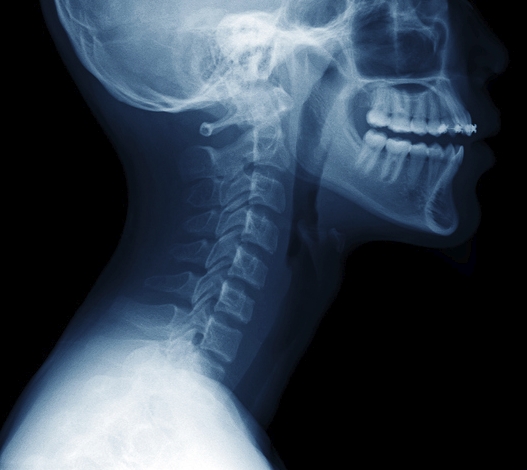

목디스크란?

목디스크는 목뼈(경추) 사이에 있는 디스크(추간판)가 손상되거나 탈출하면서 신경을 압박하는 질환입니다. 스마트폰과 컴퓨터를 많이 사용하는 현대인들에게 흔히 발생하는 문제로, 목 통증을 넘어 어깨와 팔, 손까지 영향을 줄 수 있습니다. 저도 한동안 잘못된 자세로 앉아 있는 습관 때문에 목이 뻐근하고 저린 증상을 겪었는데, 그냥 피로 때문이라 넘겼다가 더 심해진 경험이 있습니다.

목디스크의 원인

목디스크는 한순간에 생기는 것이 아니라, 오랜 습관이 쌓이면서 발생하는 경우가 많습니다. 대표적인 원인은 다음과 같습니다.